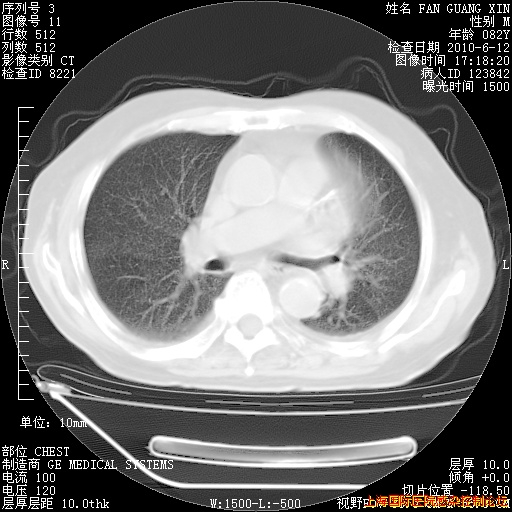

今天复查CT

今天CT

整整相隔30天的肺部CT好像有所好转啊。甲强龙减量第3天,需要观察体温。